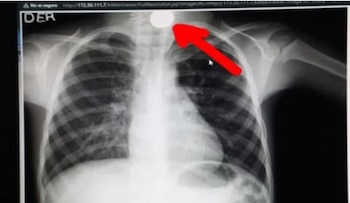

La menor, identificada con las iniciales T. H. S., presentó síntomas inmediatos: dificultad respiratoria severa, llanto persistente, irritabilidad y exceso de saliva, signos compatibles con una obstrucción de la vía aérea. Tras una primera evaluación en el Hospital Ramiro Prialé de Junín, los médicos confirmaron la presencia del cuerpo extraño mediante estudios especializados y dispusieron su referencia inmediata al Hospital Guillermo Almenara de EsSalud, considerado centro de referencia nacional para este tipo de intervenciones de alta complejidad.

Ya en Lima, el caso fue asumido por el Servicio de Cirugía de Tórax del Hospital Almenara. El Dr. Carlos Figueroa Alfaro, especialista del área, realizó una evaluación inmediata y dispuso la ejecución de una broncofibroscopía de emergencia, procedimiento clave para visualizar y acceder al interior de las vías respiratorias sin necesidad de una cirugía abierta. La intervención se realizó en un contexto de alto riesgo debido a la edad de la paciente y a la naturaleza del objeto aspirado.

Gracias a la precisión quirúrgica del equipo médico, el alfiler fue retirado exitosamente, evitando complicaciones potencialmente mortales como asfixia, neumonía aspirativa o incluso un colapso pulmonar. Tras el procedimiento, la menor evolucionó de forma favorable y permanece bajo observación médica, con una recuperación que avanza de manera positiva, según informaron fuentes hospitalarias. La madre de la niña, Marilia Huamán Turco, expresó su alivio tras la intervención.